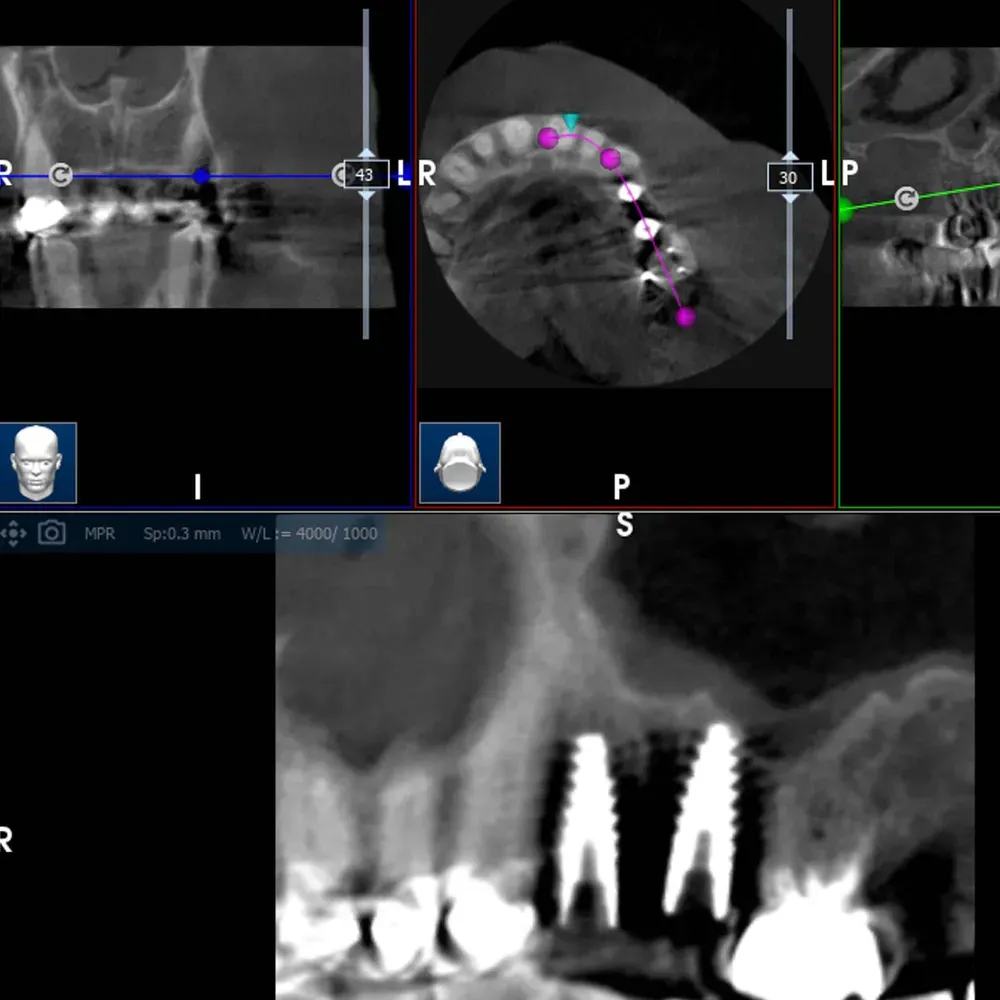

La CBCT intraoperatoria ha confermato la corretta posizione tridimensionale degli espansori e il raggiungimento della corticale del pavimento del seno in zona 2.5. In caso di dubbi sulla posizione e nel corso di interventi delicati come questo, questo ausilio strumentale è di fondamentale importanza. Ma non è sempre necessaria. L’esposizione, per quanto contenuta, dev’essere sempre ridotta al minimo, compatibilmente con la sicurezza chirurgica.

Visione laterale espansori

Sezione espansore sito 2.4

Sezione espansore sito 2.5

CBCT Post-op: Impianto in posizione 2.4 infracrestale che ha raggiunto la posizione di ingaggio corticale corretta

CBCT Post-op: Impianto in posizione 2.5 infracrestale con sollevamento della corticale del pavimento del seno